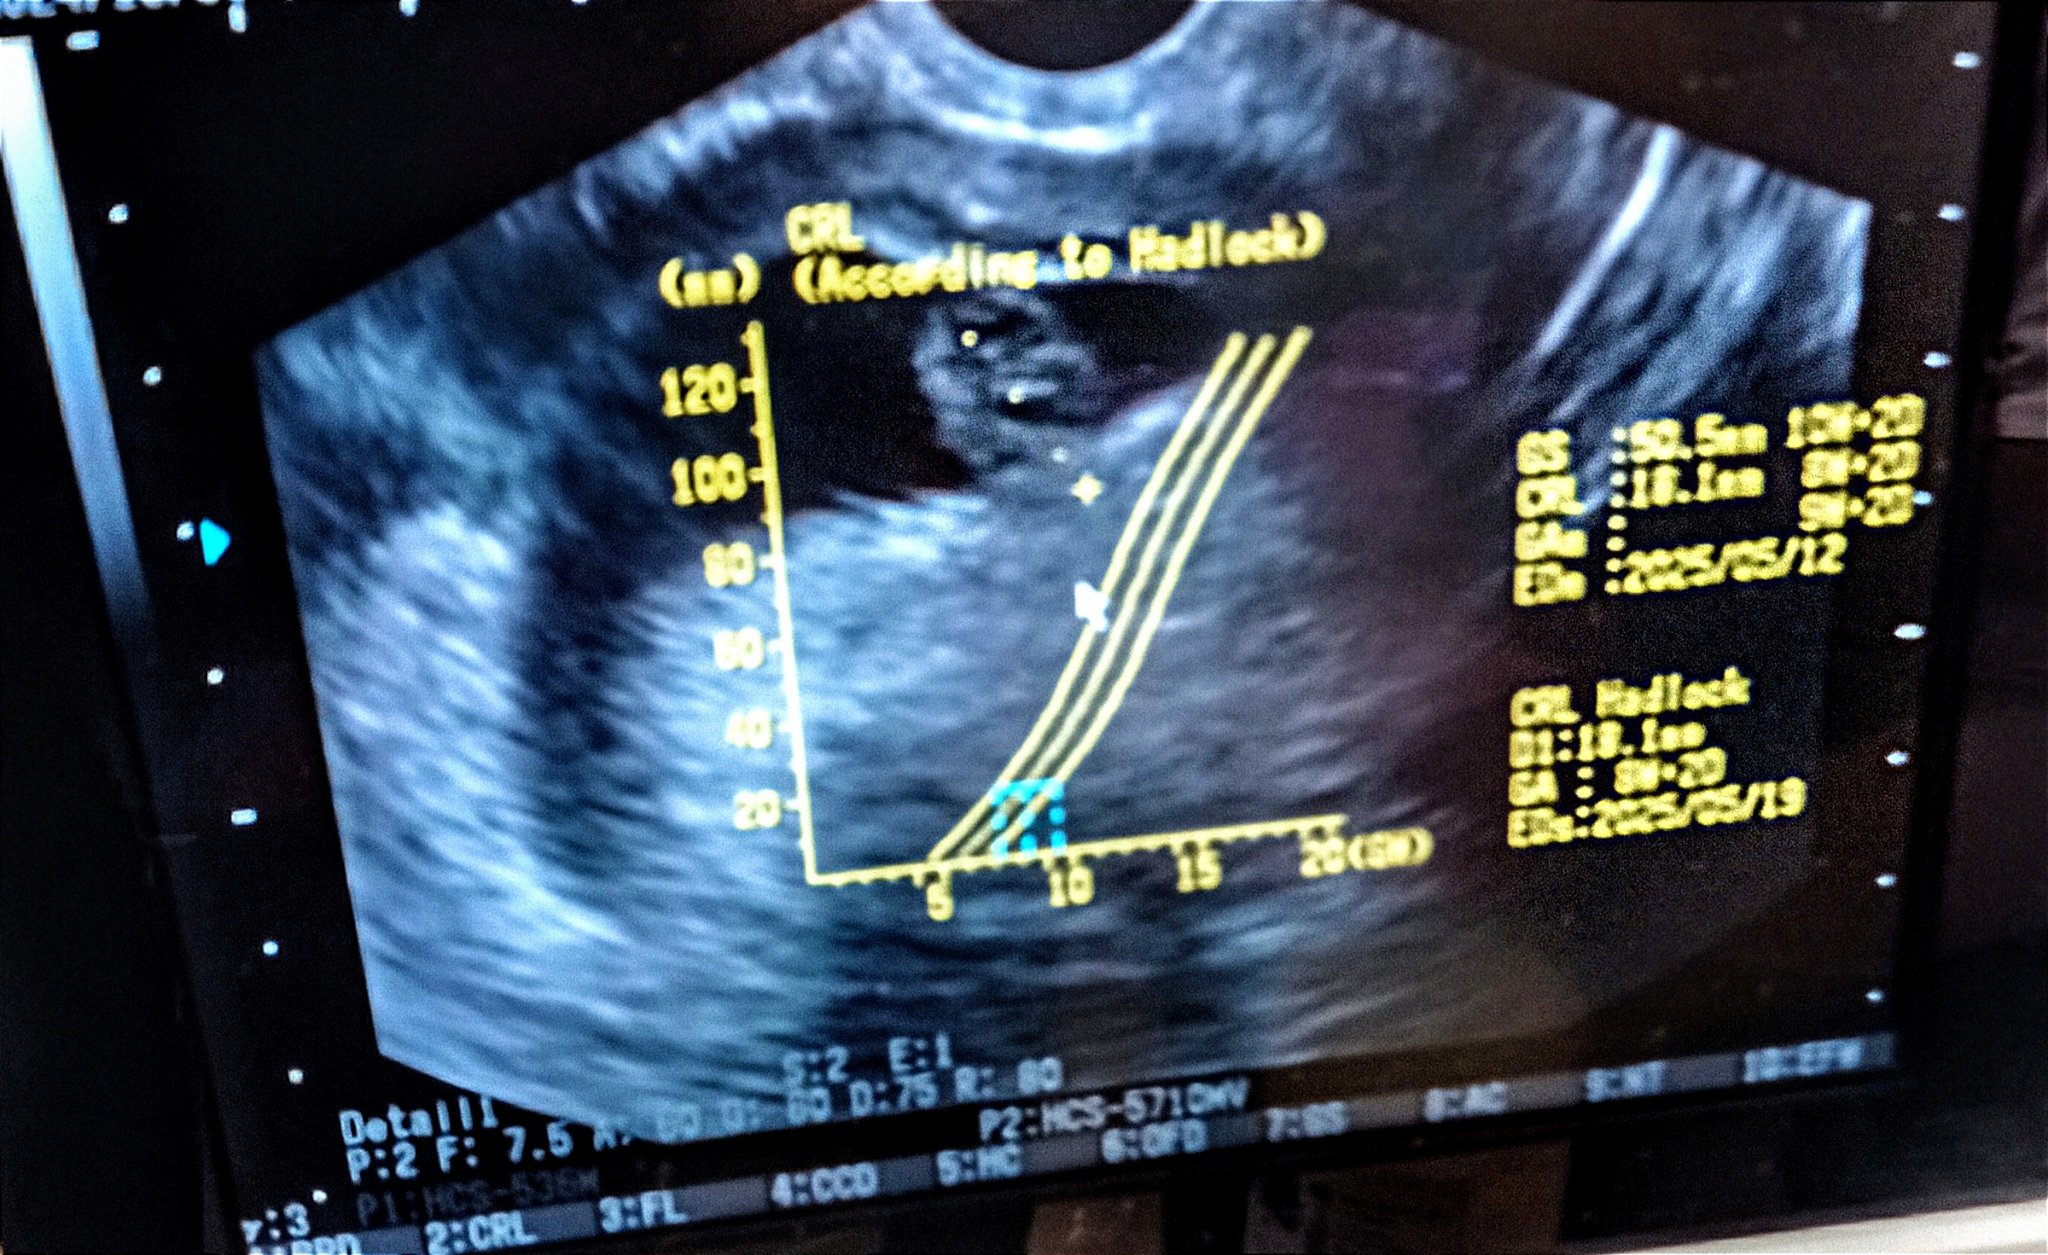

Witam. To mój pierwszy wpis. wczoraj byłam na badaniu USG i lekarz wystawił mi skierowanie do szpitala bo stwierdził odwarstwienie kosmówki i za mały zarodek. Na USG zobaczyłam dziwny kształt pęcherzyka,ale nic nie mówił na ten temat, trochę się martwię to moja druga ciąża a w pierwszej nie działu się takie rzeczy